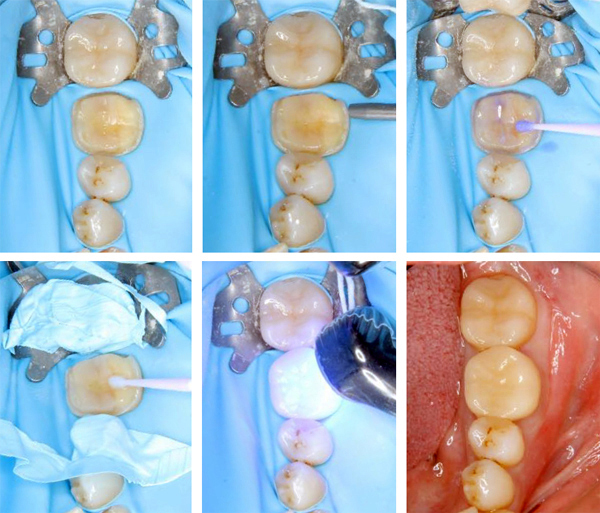

セラミック装着時には無菌で安全に

セラミック補綴物の接着時には、唾液や細菌の侵入を防ぐことが重要です。当院ではラバーダム防湿を用い、治療部位を無菌的な環境に保った状態で接着処置を行います。これにより接着力の低下や再治療のリスクを抑え、補綴物の長期安定性を高めます。